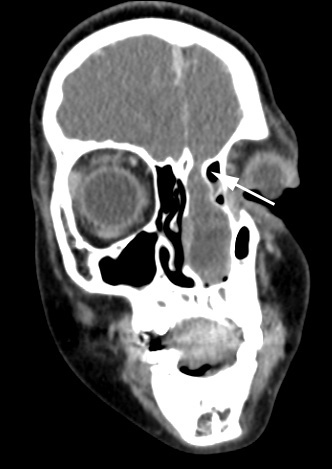

6A1,2 These coronal CT scans show a defect in the cribriform plate (arrow, 6A1) and extension of gyrus rectus tissue into the left nasal cavity.